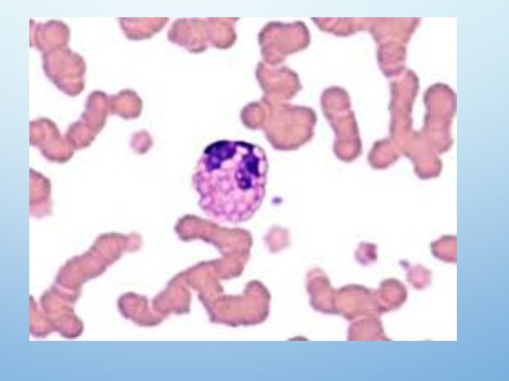

1. Identify the equine white blood cell.

2. Describe this white blood cell’s function.

A

1. Eosinophil

2. Fights parasites and mediates allergic inflammatory reactions